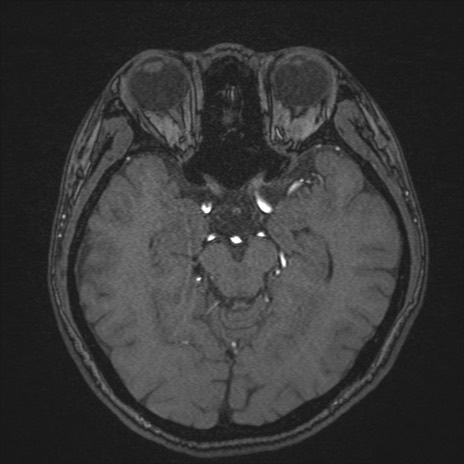

【頭部】症例44 MRI(MRA元画像)7日後

(MRA MIP像)7日後